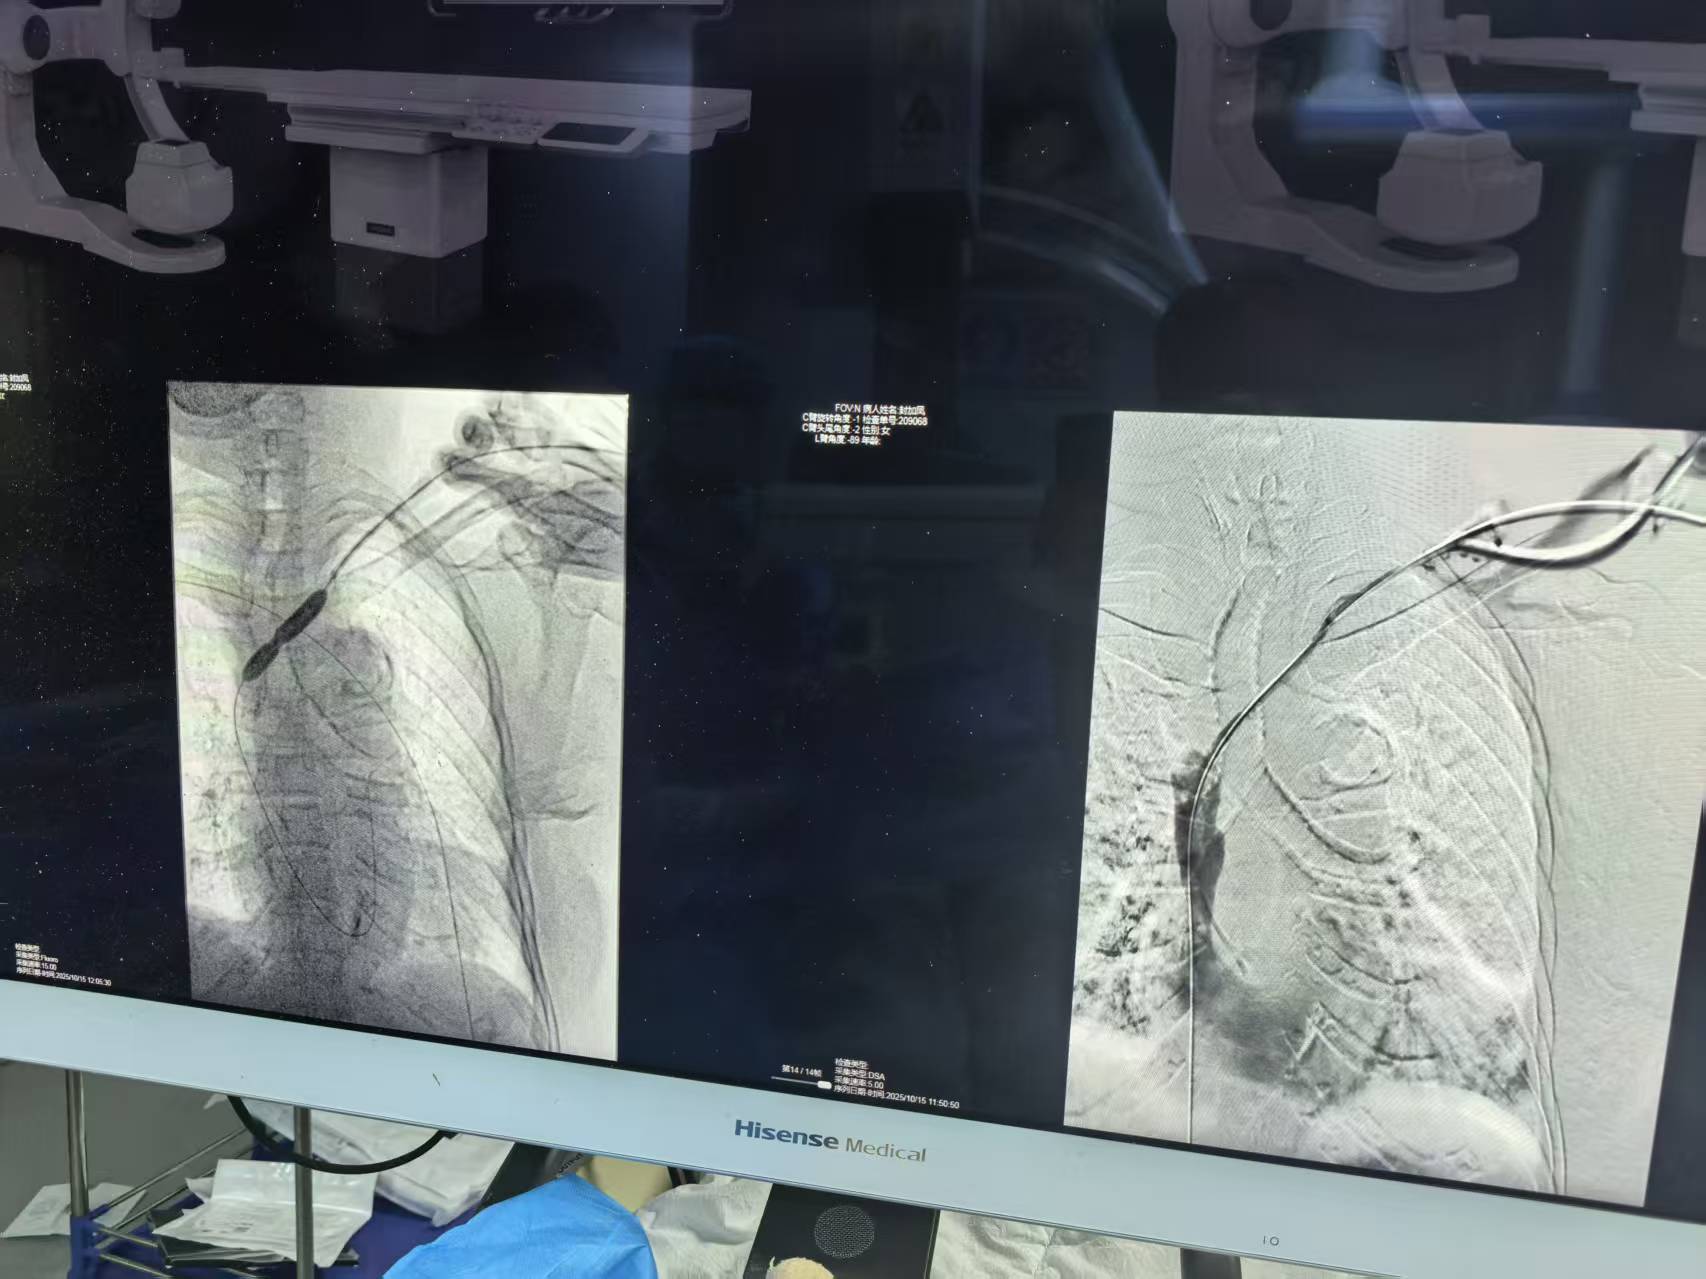

2025年10月15日上午,我院血透科冯主任带领团队,成功为一名复杂病情的住院血透患者实施了院内首例高难度长期血透导管重置手术。

面对挑战,冯主任凭借精湛技术,在DSA(数字减影血管造影)的精准引导下,于中午13时圆满完成了这台高风险手术。术后效果理想,患者及家属激动不已,由衷感谢冯主任和团队。患者更是第一时间在病友群分享喜讯,反复称赞冯主任“技术高明”,用最真实的反馈印证了我院血透科团队的专业实力。此次成功突破,为科室技术发展增添了闪亮的一笔。